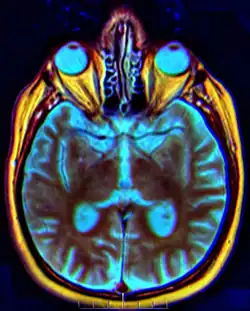

Chiasma opticum

Chiasma opticum (aus griechisch χίασμα chíasma „Kreuzung“, vom griechischen Buchstaben Chi (Χ), und der latinisierten Form des griechischen ὀπτικόν optikón „das Sehen betreffend“), auch Sehnerv(en)kreuzung, ist die anatomische Bezeichnung für die Kreuzungsstelle der Sehbahn, wo Fasern des Sehnerven (Nervus opticus) eines Auges die Seite wechseln und in den gegenseitigen Sehstrang Tractus opticus ziehen.

Im Chiasma opticum kreuzen Nervenfasern aus dem Auge einer Seite auf die Gegenseite. Das Ausmaß der kreuzenden Fasern retinaler Ganglienzellen ist bei den einzelnen Wirbeltieren unterschiedlich. Während bei Amphibien alle Fasern eines Sehnerven danach im kontralateralen Tractus opticus zu finden sind, beträgt der Anteil bei Primaten wie dem Menschen etwa 50 %. Bei dieser Halbkreuzung der Sehnerven (Semidecussatio nervorum opticorum) ziehen jeweils nur die Fasern aus der medialen, nasenwärts (nasal) gelegenen Hälfte der Netzhaut zur gegenüberliegenden Seite und anschließend im Tractus opticus zur kontralateralen Gehirnhälfte. Die Fasern aus den lateralen, schläfenwärts (temporal) liegenden Retinahälften beider Augen bleiben dagegen ungekreuzt und ziehen im Tractus opticus zur gleichseitigen (ipsilateralen) Hirnhälfte. Für das nahezu vollständig binokular erfasste Gesichtsfeld eines Menschen ist diese Aufteilung optimal.